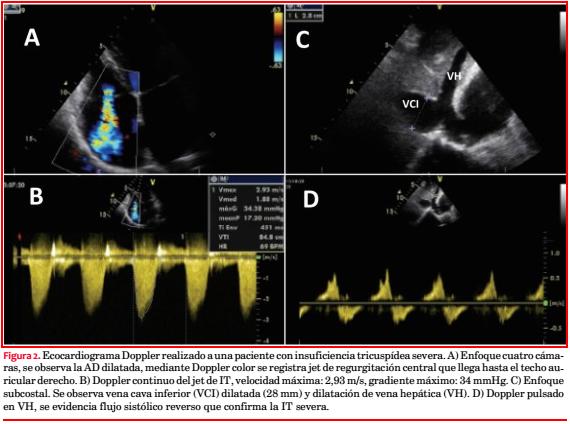

Mediante el uso de Doppler se puede lograr una estimación semicuantitativa del grado de insuficiencia. La imagen del flujo Doppler color solo se debe utilizar para el diagnóstico de IT(33) (figura 2-A). Establece las características, dirección y tamaño del jet regurgitante.

Es muy útil el registro de la IT con Doppler continuo como método no invasivo para estimar la presión sistólica del VD (figura 2-B). También interesa la dimensión de la vena cava inferior (figura 2-C) y la magnitud de su colapso para estimar la presión de la AD. La combinación de estos parámetros nos permite realizar una estimación de la presión sistólica de la arteria pulmonar (PSAP) y una aproximación al diagnóstico de HP. El Doppler de las venas hepáticas es relevante en la evaluación de la gravedad de la IT. La inversión del flujo sistólico hepático es específico de IT severa y representa un importante parámetro adicional para establecer su gravedad (figura 2-D)(33).